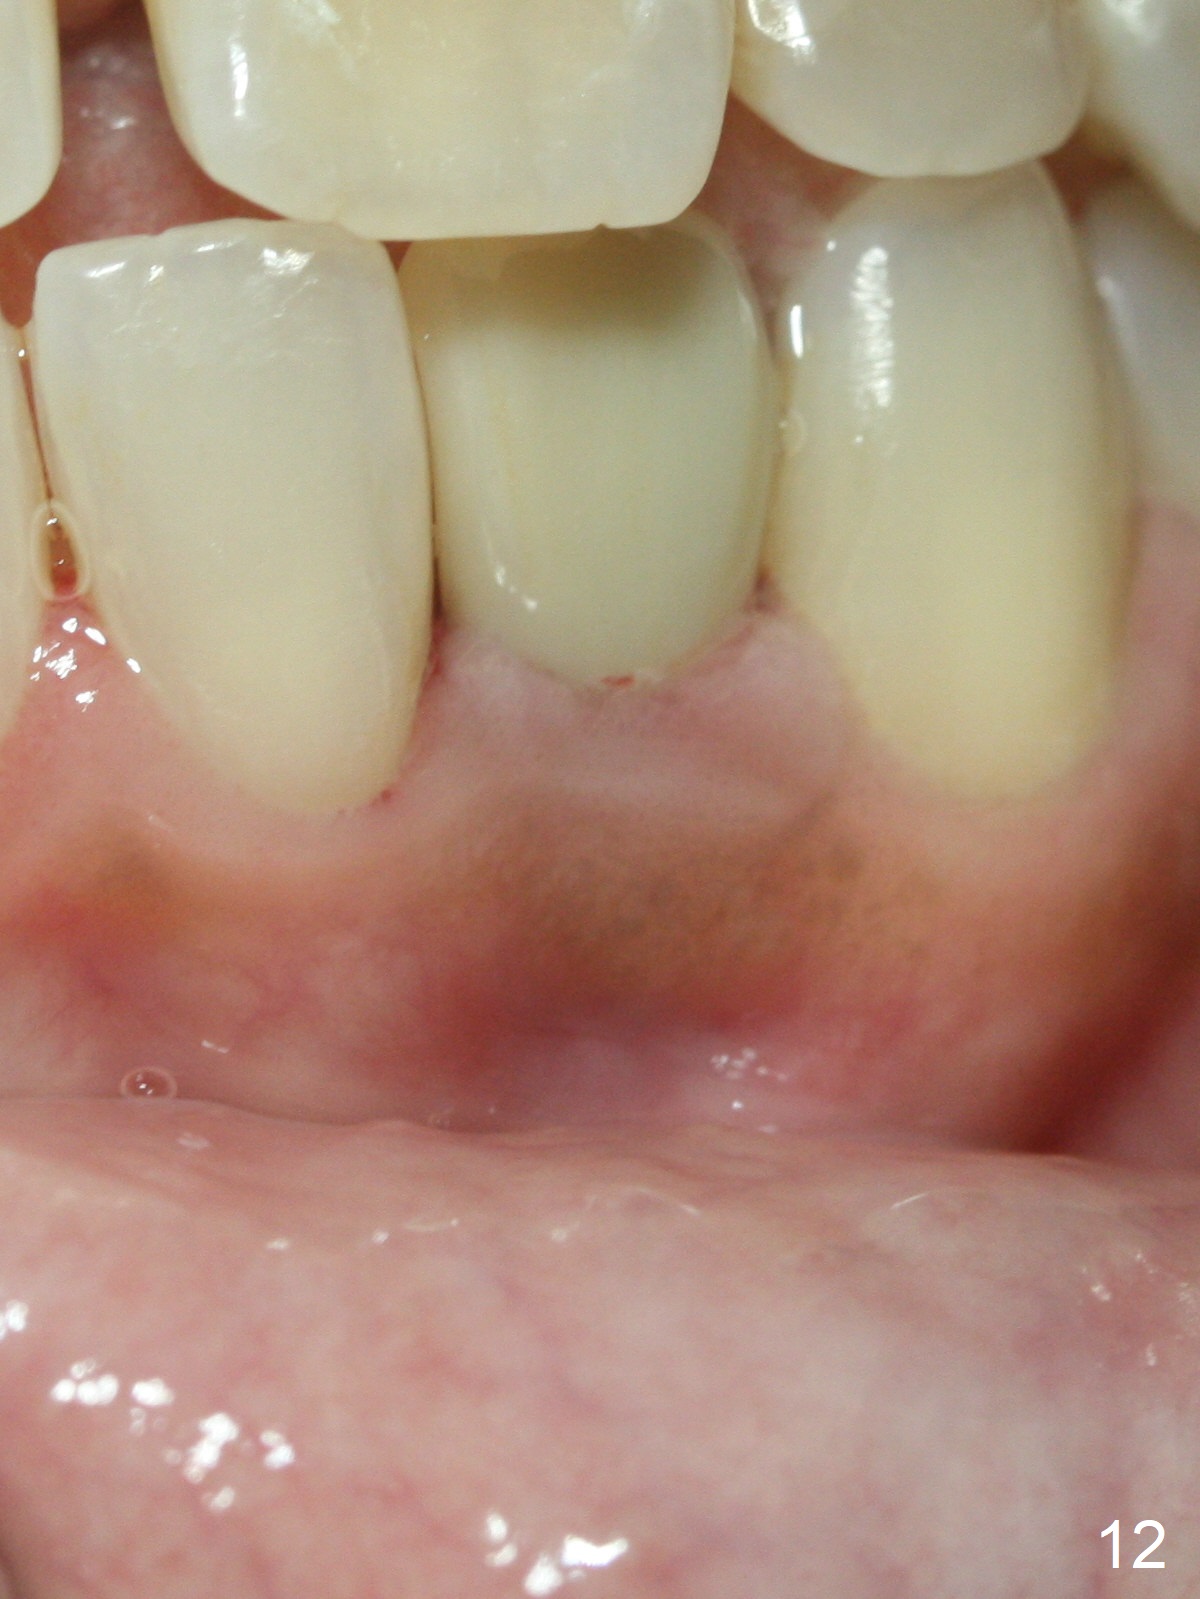

Fig.10: A2 shade guide.  The patient requests A1 for the incisal edge and body and A2.5 for the cervical region.  Fig.11 is taken 22 months post 2nd cementation (4 years postop).  The implant crown remains normal 1 year 10 months post 2nd cementation (4 years 10 months postop, Fig.12,13).